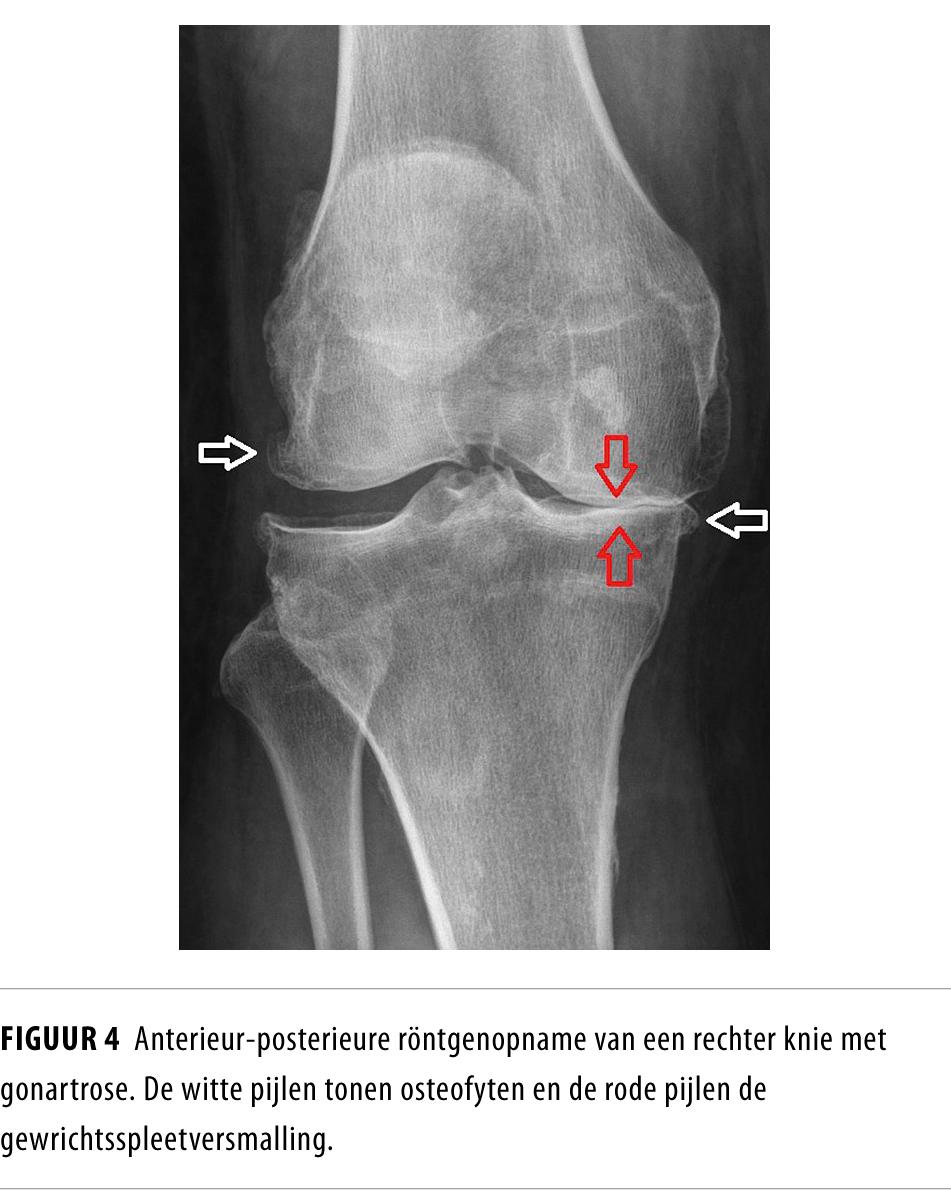

Vroeger werd artrose gezien als slijtage die leidt tot gewrichtsweefselschade en uiteindelijk tot een functiebeperking. Maar tegenwoordig wordt ze beschouwd als een uiterst complexe, multifactoriële, degeneratieve ziekte. Deze invaliderende aandoening begint op latere leeftijd en wordt gekenmerkt door verlies van articulair kraakbeen en ontsteking van het synoviale weefsel.

Waar artrose voorheen werd gezien als alleen gewrichtsslijtage, beschouwt men haar nu als een uiterst complexe, multifactoriële, degeneratieve ziekte. Door de vergrijzing en de toenemende BMI van de gemiddelde Nederlander zullen de prevalentie van artrose en de daaraan gerelateerde zorgkosten stijgen. In dit leerartikel geven wij praktische informatie over het ziektebeeld, de diagnostiek en de behandeling. Dit doen wij aan de hand van 10 vragen die leven bij onder anderen huisartsen, internisten en chirurgen.